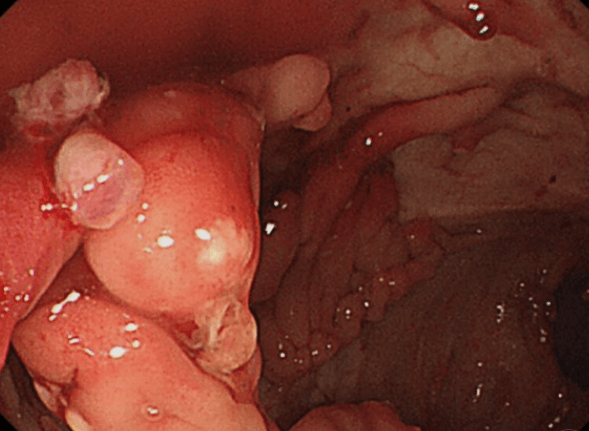

크론병은 소화기관의 만성적인 염증으로 인해 장이나 직장의 어느 부분에서든 발생할 수 있는 질환입니다.

이러한 염증은 장관벽을 손상시키고, 다양한 증상을 유발할 수 있습니다.

크론병은 그 증상과 심각도가 다양하기 때문에, 정확한 진단과 조기 치료가 필요합니다. 이러한 진단을 위해서는 내시경 검사, 혈액 검사, X-선 등의 검사가 필요합니다. 이러한 검사는 환자의 질병 상태를 파악하는 데 매우 중요합니다.

크론병은 소화기관의 염증으로 인해 다양한 증상을 유발합니다.

이 증상에는 복부 통증, 설사, 체중 감소, 혈액이 섞인 변 등이 포함됩니다.

따라서, 정확한 진단을 위해서는 내시경 검사, 혈액 검사, X-선 등의 검사가 필요합니다. 이러한 검사는 환자의 질병 상태를 파악하는 데 매우 중요합니다.